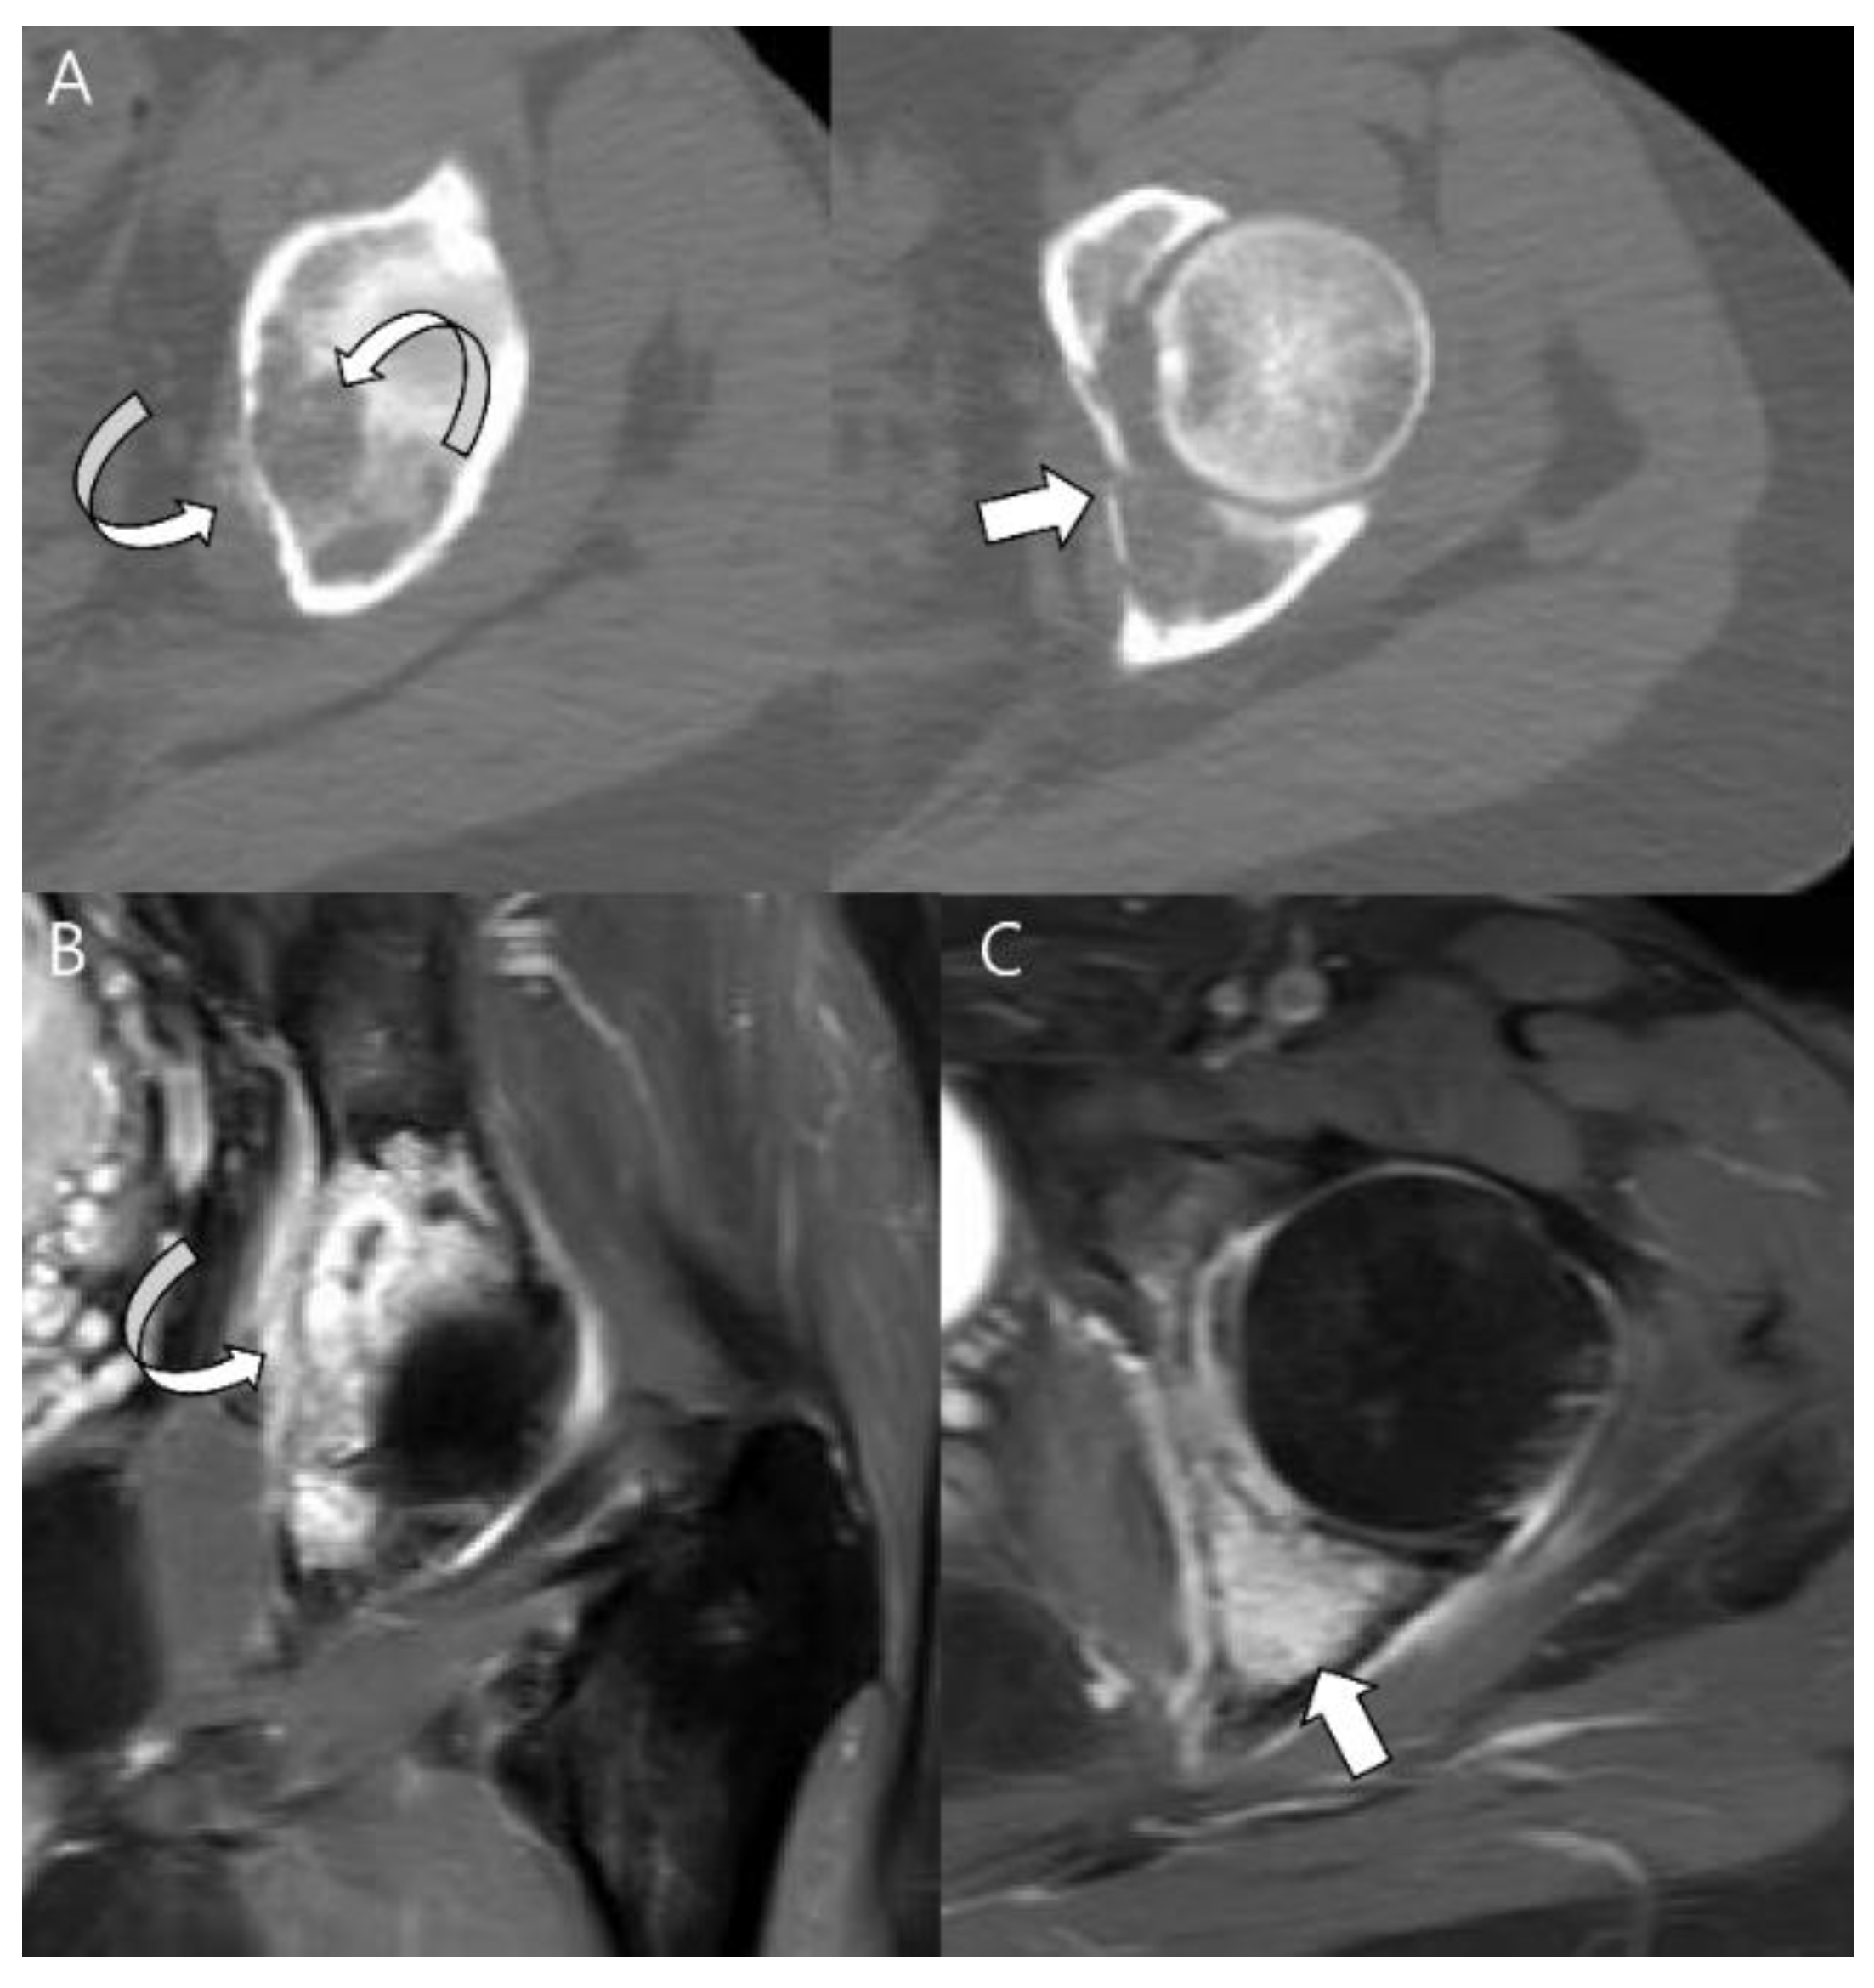

Figure 3.

Atypical cartilaginous tumor of the distal femur in a 50-year-old woman. (A) Anteroposterior and lateral radiographs reveal a mixed lytic and sclerotic lesion in the distal femur (arrows) with typical ring-and-arc calcifications. (B) Computed tomography and (C) axial T2-weighted image demonstrate a lobulated chondroid tumor with deep endosteal scalloping (curved arrows) despite the small tumor size (1.7 cm).

Figure 4.

A typical cartilaginous tumor of the humerus in a 43-year-old woman. (A) Radiographs reveal a mixed lytic and sclerotic lesion in the humerus (arrows) with typical ring-and-arc calcifications. (B) Coronal T2-weighted image with fat suppression and (C) T1-weighted enhanced image demonstrate a lobulated chondroid tumor with longitudinal endosteal scalloping (arrows) along the 9 cm length of the tumor.